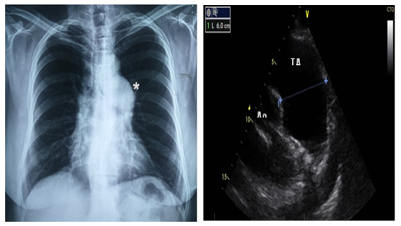

Chest x-ray without cardiomegaly, with prominent pulmonary artery cone; Electrocardiogram in sinus rhythm, normal; Transthoracic echocardiogram with aneurysmal dilatation of the pulmonary artery trunk (TAP), maximum diameter of 60m, extending to the emergency of the left branch with a diameter of 37mm, pulmonary artery systolic pressure of 30mmHg, wall thickness of the right ventricle of the right ventricle 10mm without pulmonary valvular pathology; In the Angiotomography the TAP dilatation of 58/67 / 63mm is corroborated, in the proximal,mid and distal segments, extending to the left main branch with a diameter of 35mm. Tests of renal, hepatic and thyroid function were normal; Autoimmune markers (antinuclear antibodies, anti-Sm antibodies and anti-DNA antibodies), antistreptolysin O, rheumatoid factor, VDRL and C-reactive protein, all of them were negative; Serology for Rubella, Toxoplasma, Mononucleosis, Brucella, Chlamydia, Aspergillus fumigatus and Candida were negative; Negative blood culture; Tumor markers Ca 19-9, Ca 125, Carcinoembryonic Antigen and Alpha Fetoprotein were normal. The existence of vasculitis or Marfan syndrome was dismissed, so it was concluded that it is idiopathic. Only medical surveillance is decided.The patient remained asymptomatic and unchanged in the TAP dimensions by echocardiogram at three months of follow-up.

Figure 1 X-Ray and Echocardiography image correlation.